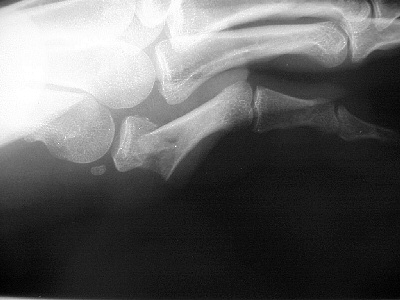

| Proximal phalanx fractures are a common problem with many treatment options. These images illustrate a technique of stabilization using intramedullary Herbert screws placed percutaneously through the base of the proximal phalanx. Provisional fixation is obtained with K wires which are replaced with Herbert screws, which simply follow the soft tissue path of the pin tract to the bone. Self tapping screws are not used in this technique, as the cutting threads catch on soft tissues. |

| One of the problems with completely displaced proximal phalanx fractures is a tendency to redisplace after temporary percutaneous pinning. This fracture was treated acutely. |